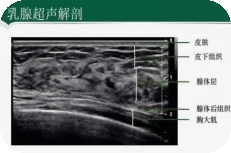

乳腺超声检查是利用超声波技术,通过探头在乳房皮肤表面移动,将声波反射形成的图像实时显示在屏幕上。医生通过观察这些图像,可以清晰地看到乳腺内部的结构、腺体、脂肪组织以及是否有异常病灶。

正常乳腺超声图